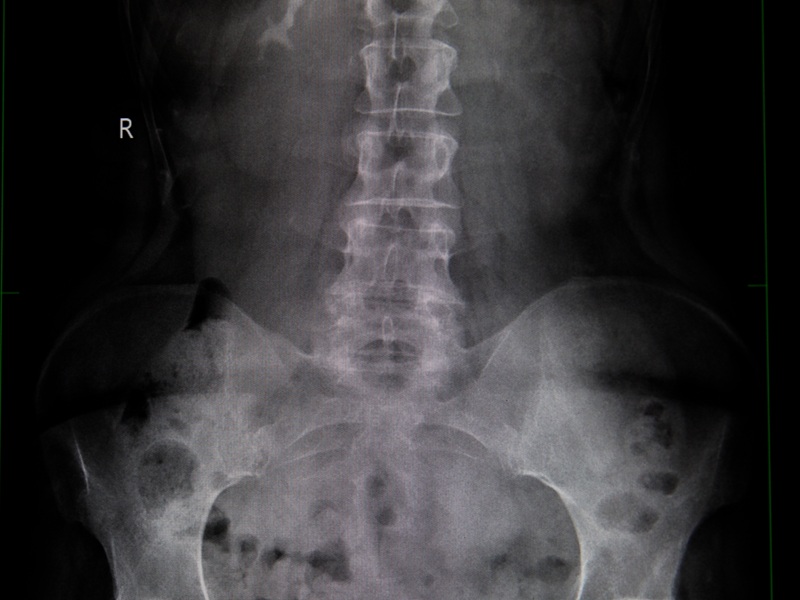

Цифровий рентген таза — це метод променевої діагностики. Медична візуалізація, що дозволяє отримати зображення кісткових структур у області таза, включаючи кульшові суглоби, крижову кістку, куприк і стегнові кістки. Завдяки рентгену лікар бачить навіть незначні зміни у кістковій тканині, наявність травм, дегенеративних процесів або аномалій розвитку.

Що показує рентген таза

Рентгенографія тазових кісток — це діагностика переломів, тріщини кісток після падінь і травми тазу. Також рентген дає можливість:

- оцінити стан при артрозі чи дисплазії кульшових суглобів;

- діагностувати вроджені або набуті деформації, в тому числі вікові зміни тазових кісток;

- побачити наслідки запальних або дегенеративних змін (наприклад, остеоартриту);

- контролювати ефективність лікування (також проводиться післяопераційна діагностика);

- оцінити симетрію суглобів та положення кульшових кісток у дітей.

Рентген малого таза у жінок використовують для виключення аномалій будови таза або при підготовці до пологів. У травматології — для точного підтвердження ушкоджень. У педіатрії — для своєчасного виявлення дисплазії.